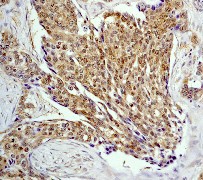

Images |

A. Western blot analysis on293T cell lysate using anti-p70 S6 kinase (N-term) RabMAb (Cat. APR08911G), dilution 1:10,000.

B. Immunohistochemical analysis of paraffin-embedded human breast adenocarcinoma using anti- p70 S6 kinase (N-term) RabMAb (Cat. APR08911G). |